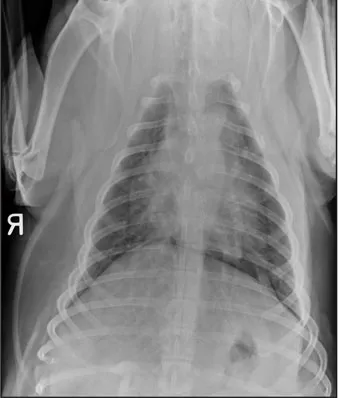

CASE 1.1 A 7-year-old neutered male Labrador Retriever who was hit by a car. You obtain these thoracic radiographs: Figs. 1.1a, b, left and right lateral projections, respectively; Figs. 1.1c, d, ventrodorsal and dorsoventral projections, respectively.

1.1c